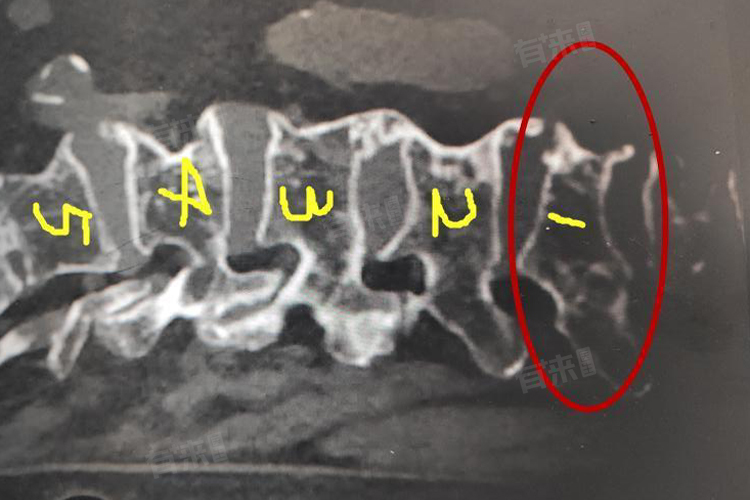

3、诊断方法

- 可以通过X射线、CT及磁共振成像检查判断,X射线可初步判断骨折的部位、程度和类型。CT能更详细地显示骨折的细节,评估骨折对椎管的影响。磁共振成像有助于判断脊髓是否受损以及软组织的损伤情况。